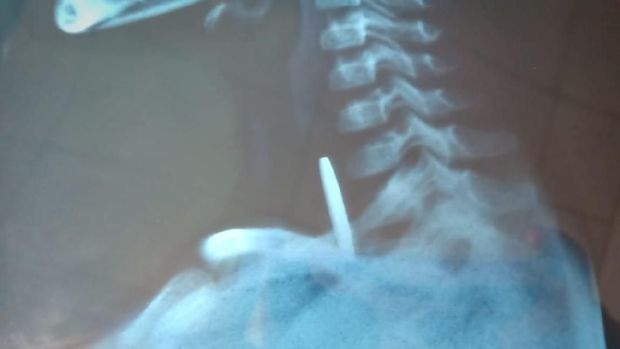

Hasil rongent Noverius. Foto: Dok. Onlihu |

Dari hasil pemeriksaan Rontgen RSUD Gusit, kondisi kepingan logam itu cukup membahayakan karena tertahan dekat jantung. Menurut Onlihu, Nocerius kondisinya sudah mulai lemah.

Hasil rongent Noverius. Foto: Dok. Onlihu